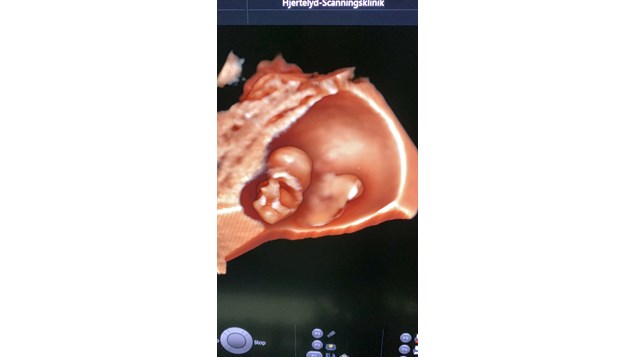

Her er det en lille foster på bare 23 mm.

Alderen er kun 9 uger. Alle organer er stort set skabt.

Man kan faktisk ane bitte små fingre og tæer !